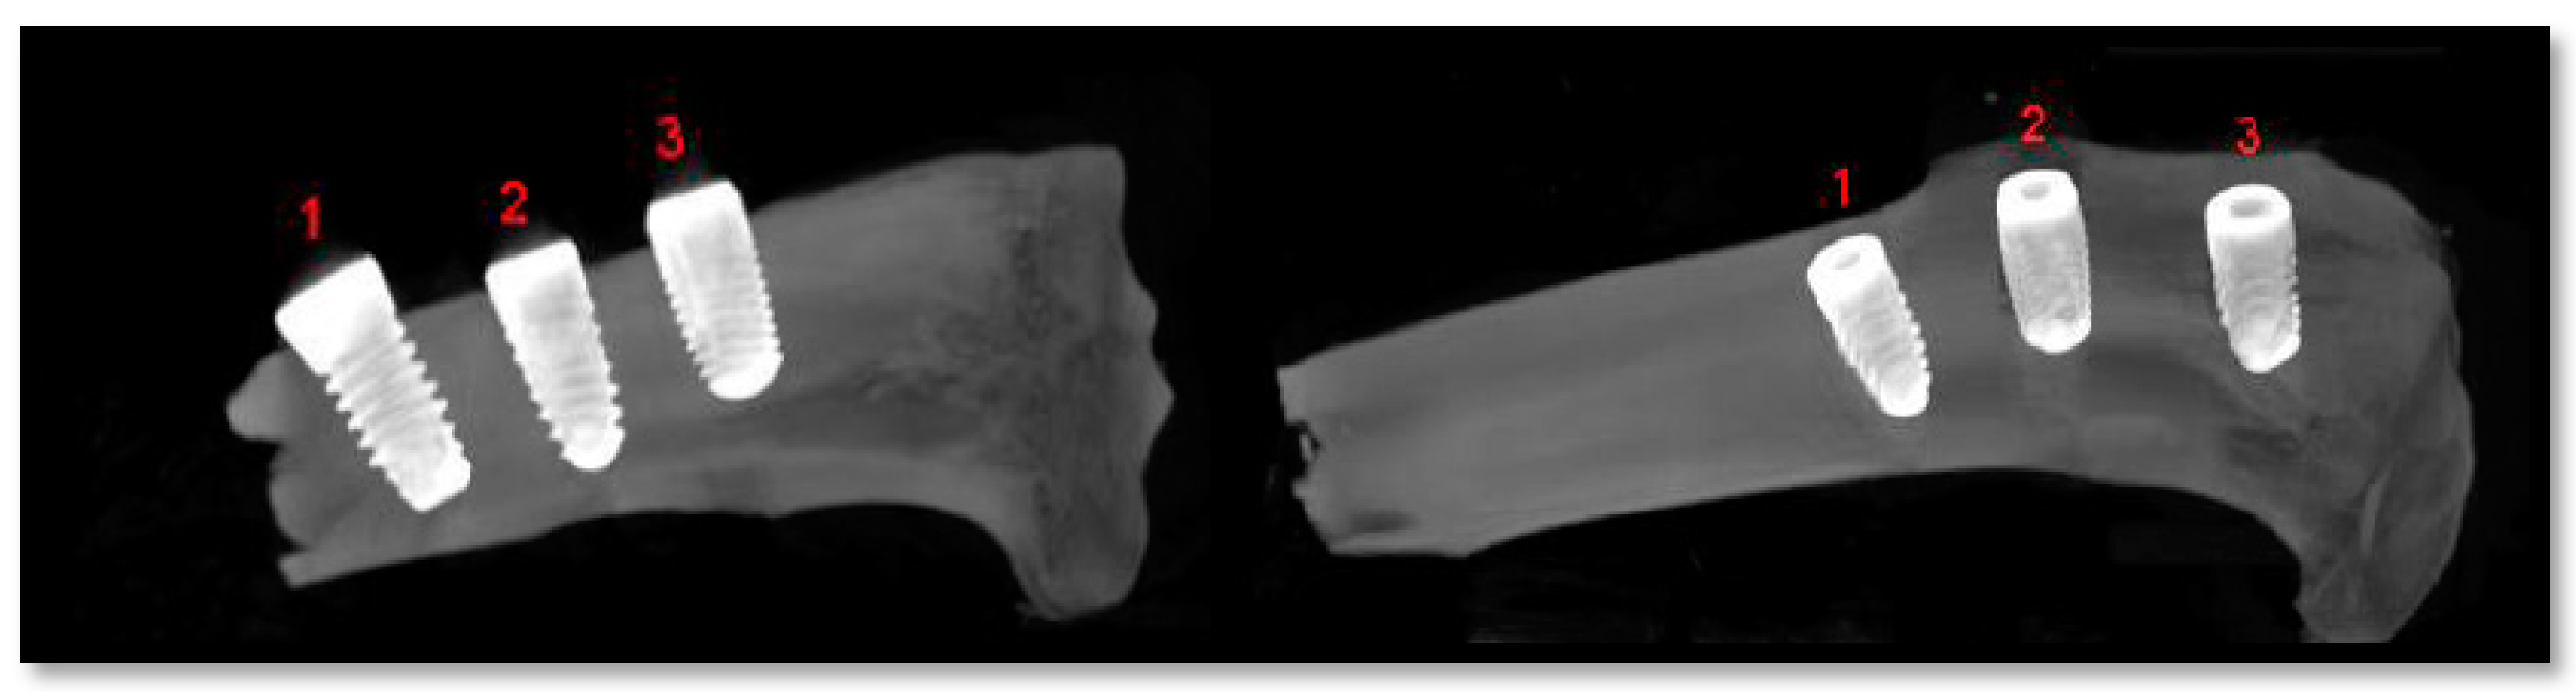

2.5. Radiological Analysis

3.3. Experimental Animal Study